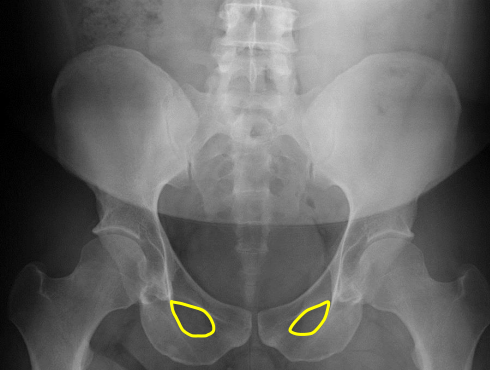

Obturator foramen